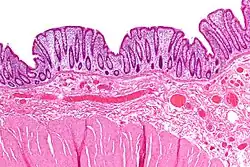

Solitary rectal ulcer syndrome

Solitary rectal ulcer syndrome (SRUS, SRU) is a chronic disorder of the rectal mucosa (the lining of the rectum).[41] Symptoms are variable. There may be hematochezia (bleeding), obstructed defecation, or no symptoms at all.[42][43][44] Very often but not always SRUS occurs in association with varying degrees of rectal prolapse.[41] The condition may be caused by different factors, such as long term constipation, straining during defecation, and dyssynergic defecation (anismus).[42][45] Treatment is by normalization of bowel habits,[41] biofeedback,[45] and other non-surgical measures. In more severe cases, various surgical procedures may be indicated.[45][42] The condition is relatively rare, affecting approximately 1 in 100,000 people per year.[44] It affects mainly adults aged 30–50.[44] Females are affected slightly more often than males.[41] The disorder can be confused clinically with rectal cancer or other conditions such as inflammatory bowel disease, even when a biopsy is done.[46]

Colitis cystica profunda

Another condition associated with internal intussusception is colitis cystica profunda (also known as CCP, or proctitis cystica profunda), which is cystica profunda in the rectum. Cystica profunda is characterized by formation of mucin cysts in the muscle layers of the gut lining, and it can occur anywhere along the gastrointestinal tract. When it occurs in the rectum, some believe to be an interchangeable diagnosis with SRUS since the histologic features of the conditions overlap.[47][48] Indeed, CCP is managed identically to SRUS.[49]